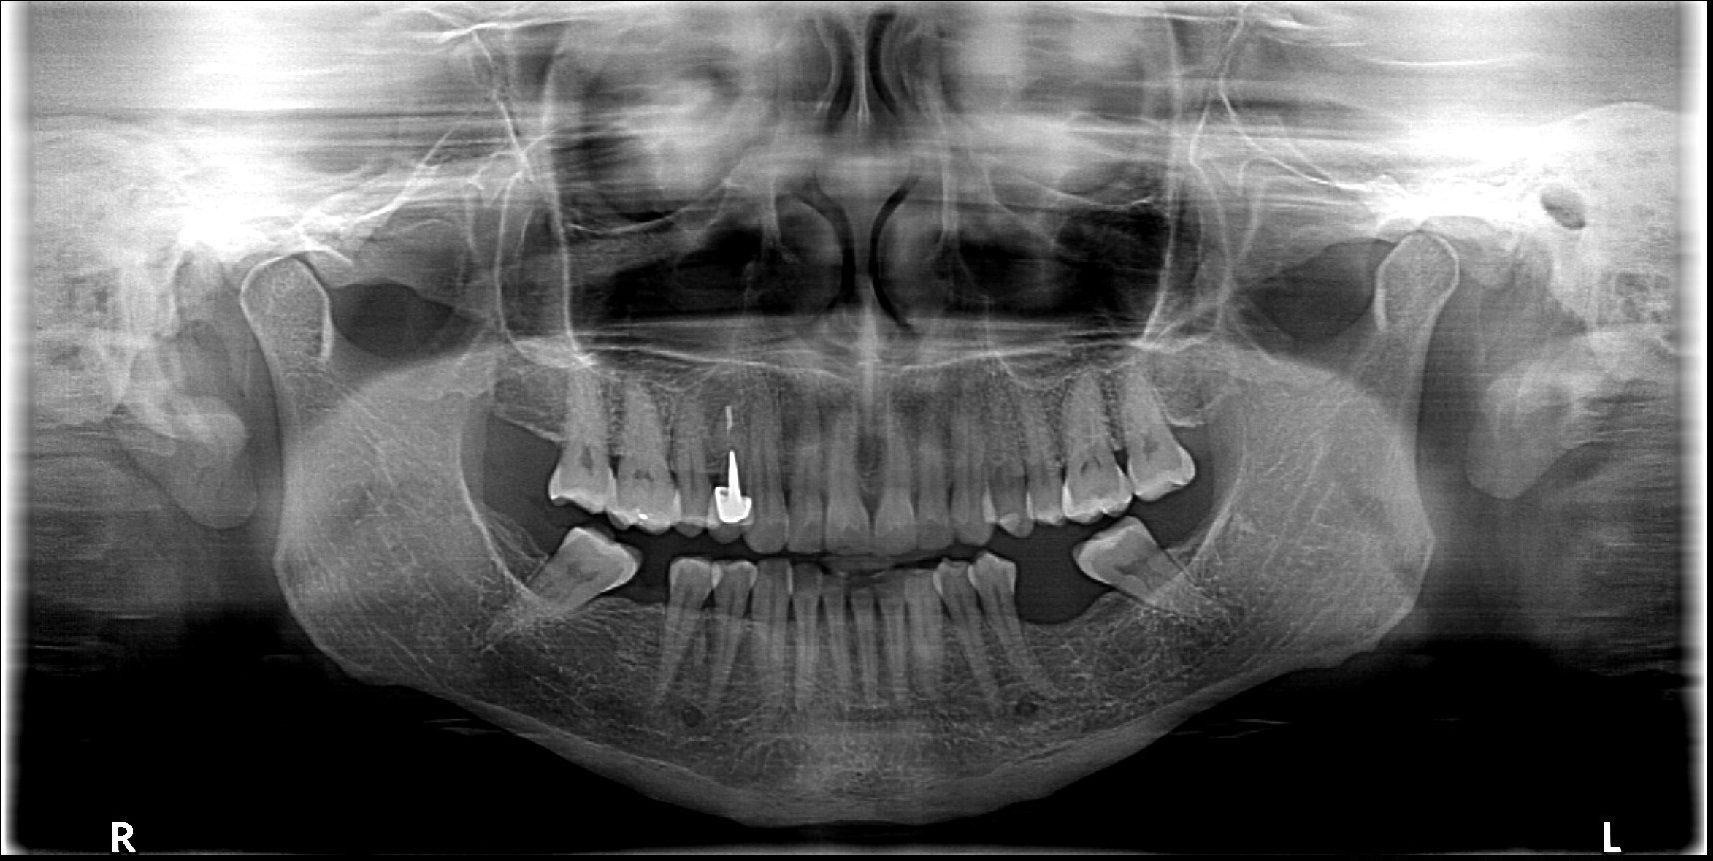

Contar con la más moderna tecnología permite una óptima visualización de piezas dentarias y estructuras óseas, articulares y musculares.

A las técnicas tradicionales como la radiología, sumamos estudios de avanzada para asistir a las prácticas de alta complejidad médica incluyendo la Tomografía Computada Cone Beam el más moderno sistema de imágenes odontológicas y maxilofaciales.